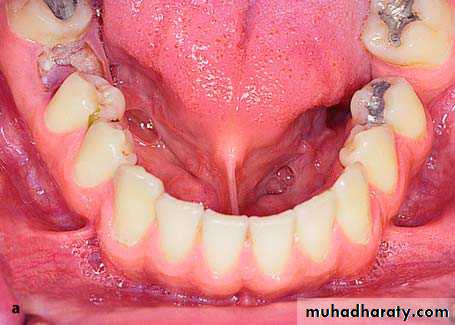

Multiple Exostoses

These are rare asymptomatic bony excrescences, usually localized at the buccal surface of the maxilla and mandible. The causes are unknown, although some people suggest that they may be due to bruxism as well as chronic irritation of the periodontal tissues. No therapy is usually required, except for those cases where, due to the large size of the exostoses, severe esthetic and functional problems are created.

Extremely large multiple exostoses in the maxilla with a multilobular and irregular shape